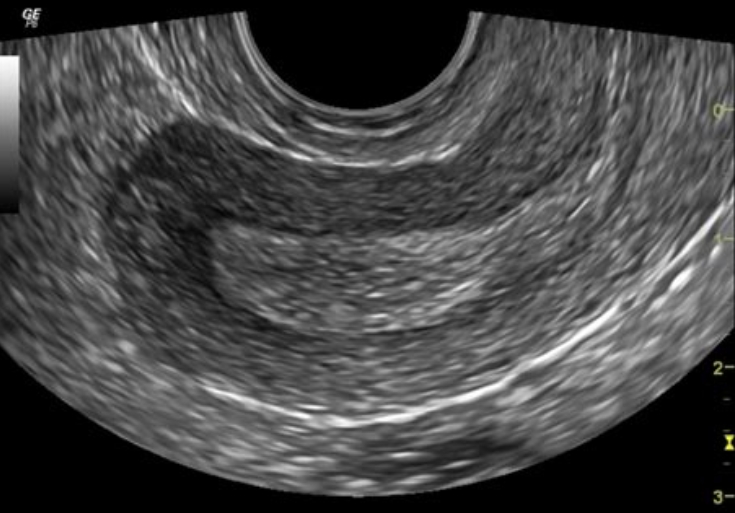

Существуют два основных подхода. Трансабдоминальный датчик скользит по передней брюшной стенке и даёт обзорную картину; для чёткости пациентке предлагают наполнить мочевой пузырь. Трансвагинальный датчик вводят во влагалище на небольшую глубину: пустой пузырь и близость зонда к органам обеспечивают более детальную визуализацию матки, эндометрия и яичников. Оба варианта могут дополняться допплеровским режимом, позволяющим оценивать кровоток.

Что именно видно на экране

На УЗИ врач определяет размеры, форму и контуры матки, толщину и структуру эндометрия, положение и эхогенность яичников, наличие доминантного фолликула или жёлтого тела, а также возможные кисты, миомы, полипы, очаги эндометриоза и свободную жидкость в полости таза. При необходимости измеряется скорость кровотока, что помогает отличить доброкачественные процессы от злокачественных. Специалистам и практикующим врачам рекомендуем онлайн тесты по УЗИ.